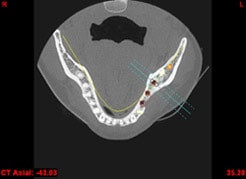

In komplexen Fällen, z. B. der Implantatversorgung eines kompletten Kiefers, oder bei schwierigen Knochensituationen bietet die 3-dimensionale Computerdiagnostik bzw. Planung und Durchführung erhebliche Vorteile und Sicherheit für den Patienten (siehe Bild 1 und 2).

Auf Basis einer computertomografischen (CT-) Kieferaufnahme ist eine dreidimensionale Darstellung der Knochen möglich. Der Zahnarzt kann dann am Computerbildschirm die Knochenqualität (z. B. Knochendichte) beurteilen und die optimale Position der Implantate im Vorfeld planen. Durch Verwendung spezieller Röntgenschablonen lässt sich auch die erwünschte Zahnstellung in die Planung einbeziehen. Die Simulation der OP erlaubt, das zu erwartende Ergebnis mit größtmöglicher Sicherheit vorherzusagen und dem Patienten am Bildschirm zu veranschaulichen.